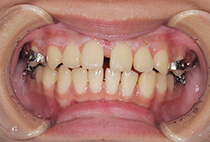

外科矯正なしで「顎のずれを整えたい」と来院された20代女性。

精密検査の結果、原因は骨格の非対称だけでなく、

かみ合わせ・咬合平面の傾き、そして左右非対称な筋肉の肥大でした。

1年3ヶ月の非抜歯矯正で、ずれていたかみ合わせが改善。

唇側矯正、インプラントアンカー、美容治療

治療後はさらにフェイスラインの左右差を整えるため、オトガイ部・頬のふくらみにヒアルロン酸注射を施し、よりバランスの取れた美しい顔立ちに。